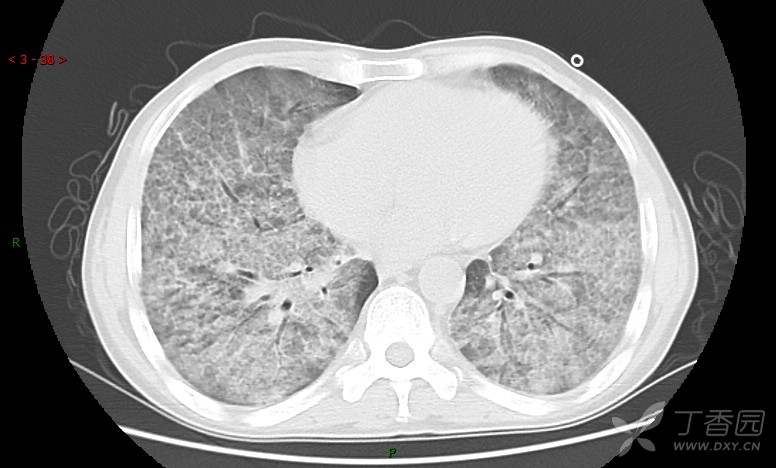

地图+铺路石征=PAP?那升高的CEA怎么说(病例3连发,附其他2例链接)

患者男,42岁,咳嗽半年余,加重伴憋喘2月余。

患者半年余前无明显诱因出现间断咳嗽,干咳为主,偶咳少量黄白痰,剧烈咳嗽或运动后可出现轻度憋喘,无高热、脓臭痰,无胸痛、咯血及晕厥,无低热乏力及盗汗,无心前区压榨感及夜间阵发性呼吸困难,初未在意,未予正规诊治。2月余前患者自觉上述症状较前加重,咳嗽、憋喘明显,黄白色粘痰略有增多,伴有发热,热前伴有畏寒、寒战,体温最高达38.9℃,先后就诊多家医院,入住重症监护室,未行气管插管,考虑“重症肺炎”,给予“美罗培南、复方磺胺甲噁唑”等药物抗感染,“卡泊芬净”抗真菌,并给予“甲泼尼龙”等药物治疗35天,经治疗后症状好转于2018-04-02出院。患者自出院后仅应用中药治疗(具体不详),并给予家庭氧疗,平素仍有间断咳嗽,咳少量黄白色粘痰,活动后憋喘明显,活动耐量差,以卧床为主。

肺内弥漫性网状结节影,PET-CT却无阳性病灶,这是?(附其他2例链接)